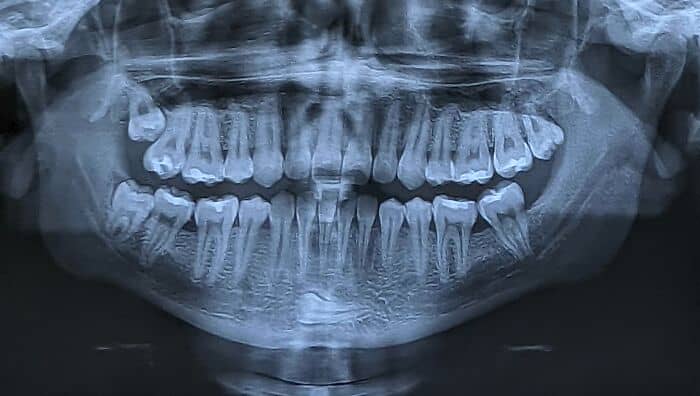

#63 This Is A Condition Called Hyperdontia